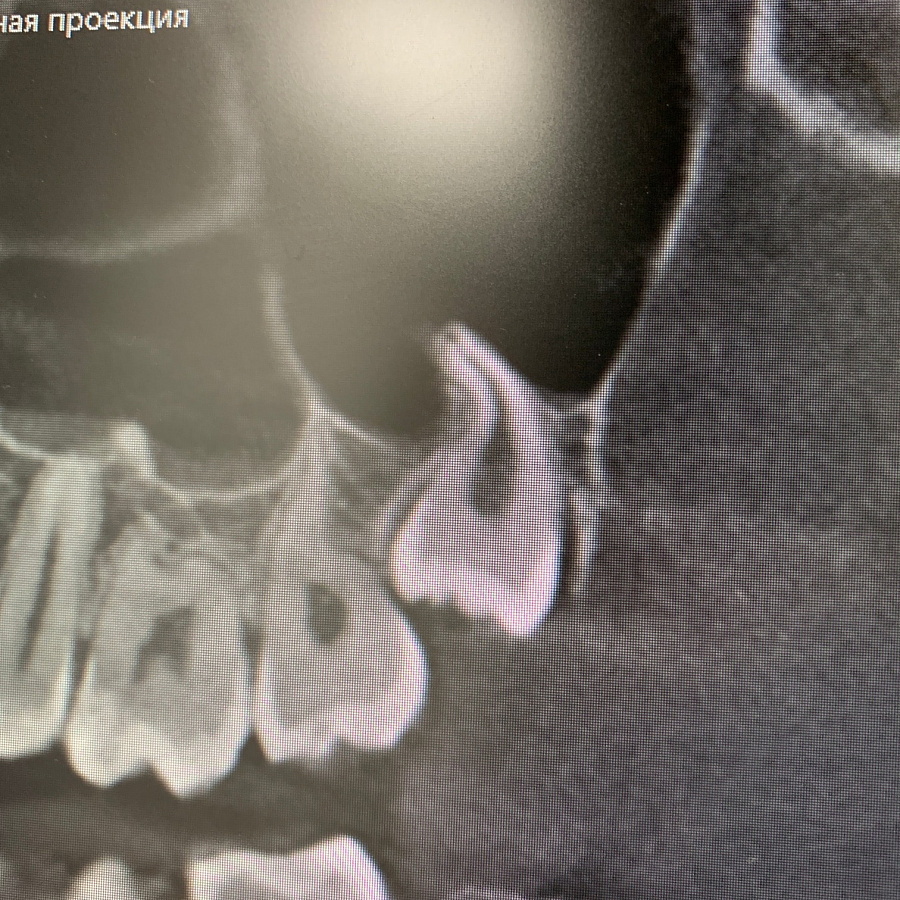

Удаление ретинированного дистопированного зуба мудрости

Удаление ретинированного дистопированного зуба мудрости на верхней челюсти слева.

Сложность данного кейса в том, что восьмой зуб упирается под углом в сторону седьмого зуба. Зуб удален полностью, дискомфорт пациент не испытывает.